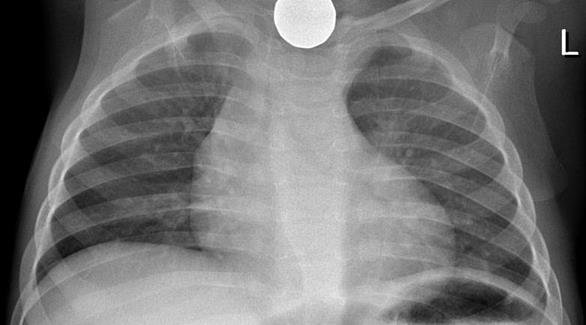

ابتلاع الأطفال عُملات معدنية من الحوادث الشائعة، وعلى الرغم من أن الأمر يبدو مقلقاً إلا أن التقارير الطبية تفيد أنه في 80 إلى 90 بالمائة من الحالات ستخرج العُملة المعدنية مع البراز خلال يوم أو اثنين. لكن في كل الأحوال عندما يبتلع الطفل شيئاً ينبغي طلب الطوارئ حتى لو لم تظهر عليه علامات غير عادية.

تحث التوصيات الطبية في حالة ابتلاع الطفل عُملة معدنية على مراقبة البراز للتحقق من خروجها. وتفيد بعض التقارير الطبية أنه في 40 بالمائة من الحالات لا يرى الآباء العُملة بعدما تخرج، وأنه كلما كان الطفل كبيراً كلما كان خروج العُملة أكثر سهولة خلال أقل من 16 ساعة بغض النظر عن حجمها.

قد تعلق العُملة بعد ابتلاعها في المرئ، أو المعدة، أو الأمعاء. في هذه الحالة يمكن استخراجها بواسطة القسطرة، أو المنظار. وفي بعض الحالات قد تكون الجراحة مطلوبة.

إذا علقت العُملة داخل موضع ما بالجسم ستظهر علامات على ذلك. من العلامات: القئ، وألم الصدر والبطن إذا كانت عالقة في المرئ أو المعدة. أما إذا علقت على جدار الأمعاء فقد تؤذي الجدار، ومن علامات وجودها في ذلك الجزء وجود صوت غريب عند إخراج البراز أو وجود نزيف معه.

من الهام أن يلجأ الآباء إلى الطوارئ، وألا تتم محاولة إخراج العُملة بالإصبع لأن ذلك سيضر الطفل أكثر. عند حدوث هذه الحادثة، أو الشك في حدوثها، لا ينبغي الانتظار وإنما طلب الطوارئ على الفور، وإجراء الفحص بالأشعة السينية (إكس)، واتباع التعليمات الطبية.